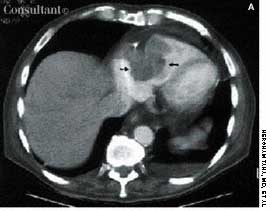

An obese 61-year-old man who had chronic obstructive pulmonary disease and sleep apnea heard a “pop” in his stomach while lifting a heavy weight; severe abdominal pain followed. In a CT scan of the abdomen and pelvis, arrows point to inflammation in the aortic wall (A) and the paraaortic retroperitoneal fat (I, inferior vena cava; K, kidney.) Calcified atherosclerotic plaques were visible, but the aorta was not dilated. There was neither retroperitoneal hematoma nor contrast extravasation to suggest rupture. The patient had aortitis.

Image courtesy of Joel M. Schwartz, MD.